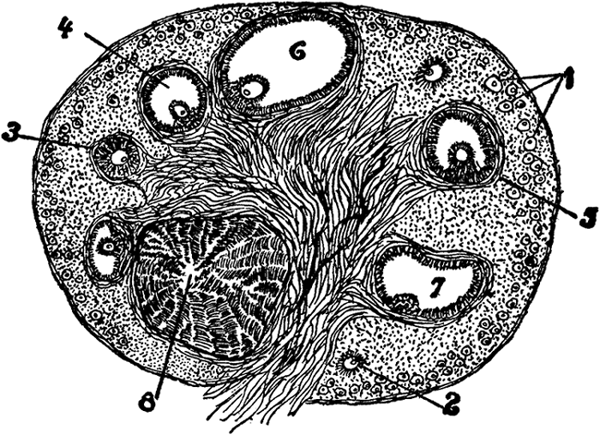

The Graafian Follicles. Each primitive or primordial ovum[3] is imbedded in a little vesicle or follicle, which is generally known as Graafian follicle, and there are as many Graafian follicles as there are ova. (The Graafian follicles were first described about 250 years ago—in 1672—by a Delft physician named De Graaf, hence the name.) Until puberty, that is the commencement of menstruation, the Graafian follicles with the oöcytes or primitive [53]ova are in a more or less dormant condition. But with the onset of puberty there commences a period of intense activity in the ovaries. This period of activity is repeated regularly once a month, and it constitutes the process of ovulation and menstruation. The two processes are closely though not causally connected. Ovulation consists in the monthly maturation and extrusion of a ripe ovum; menstruation, which will be further discussed in a separate chapter, consists in the monthly discharge of blood, mixed with mucus from the inside lining of the uterus. Every twenty-eight days, from the [54]time of puberty to the time of the menopause, a Graafian follicle bursts and an ovum is extruded from the ovary. Before the follicle bursts, it swells and enlarges and reaches the surface of the ovary; the whole follicle is congested with blood, but at one point near the surface of the ovary it is pale and thin, and here the rupture takes place.

Section of Ovary.

1. Graafian follicle in the earliest stage.

2, 3, 4. Follicles in more

advanced stages.

5, 7. Almost mature follicle.

6. Follicle from which

the ovum has escaped.

8. Corpus luteum.

Corpora Lutea. After the Graafian follicle has burst and the ovum has been pushed out, the cavity that is left does not remain empty and functionless; there is a further process going on there; there is a growth of cells, of a yellowish color, and the follicle becomes filled with a yellowish body, which on account of its color is called the corpus luteum (plural—corpora lutea; luteum in Latin—yellow, corpus—body). This corpus luteum grows in size until it sometimes occupies as much as one-third of the ovary. But there is considerable difference between the corpora lutea of non-pregnant and pregnant women. Up to the end of about a month the corpora lutea are the same, but after that the corpus luteum of the non-pregnant woman begins to get smaller, to shrink, so that at the end of two or three months it is reduced to a small scar and later cannot be noticed at all. The corpus luteum of the pregnant woman keeps on increasing until the end of the second month, remains about the same size [55]until the end of the sixth month, and only then begins gradually to diminish. The corpus luteum of the non-pregnant woman, that is, the one following menstruation, is called false corpus luteum; the corpus luteum following pregnancy is called a true corpus luteum. The corpus luteum acts like a gland and elaborates a secretion which has an influence on the circulation in the uterus and on menstruation. It probably possesses other properties, with which we are not yet quite familiar. The corpora lutea of various animals are now prepared in powder or tablet form and used in medicine in the treatment of certain diseases of women.